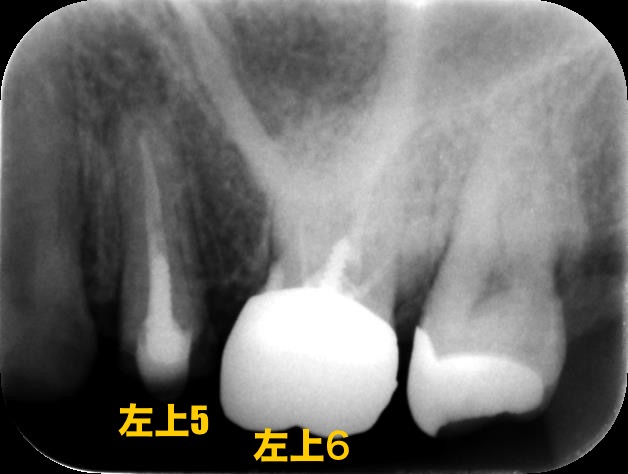

パノラマ写真を見ると、左上の5、6番目の歯だけ既に神経を失ってしまっています。

レントゲン写真もご覧下さい

根管治療がされているようですが、きちんと根の先まで薬が入っておらず神経の取り残しが見受けられます

しかしこの時には根尖病変は見受けられなかったため、先に上のかぶせ物を矯正用の仮歯に置き換えて矯正をスタートさせます